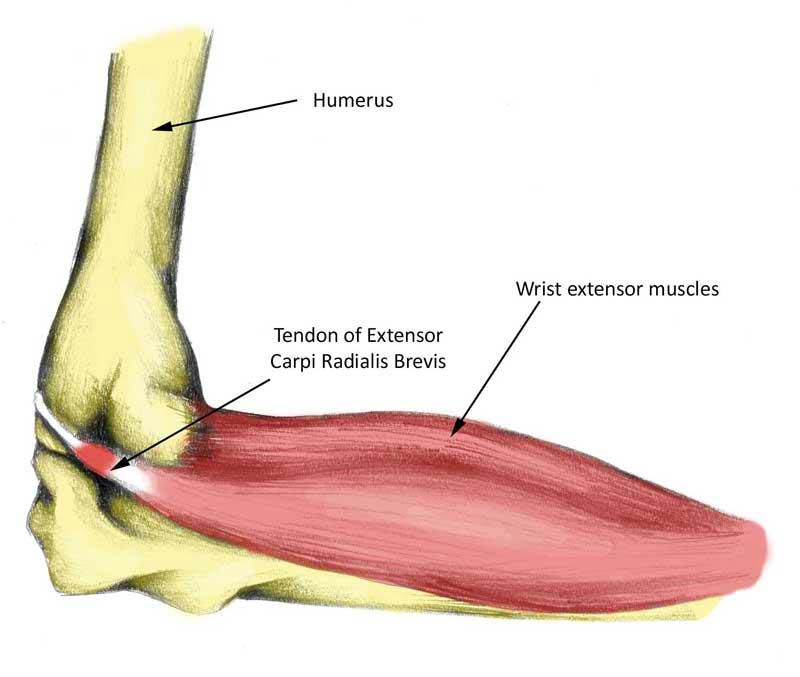

В околосуставной зоне также встречаются эпикондилиты, тендиниты, бурситы, миозиты. Патология локтя достаточно разнообразна, а причину неприятных ощущений в этой области определит лишь врач.

Мышцы, окружающие локтевое сочленение

Анатомия локтевого сустава мышечного корсета является сложным механизмом, без него движения не были бы возможными. Большинство мышц фиксируются в области плеча.

Разгибание доступно благодаря совокупности функционирования группы мышц:

Сгибание обеспечивают:

- пронатор;

- бицепс;

- плечевая и плечелучевая мышцы.

Вращение внутрь происходит за счет:

- пронатора;

- плечелучевой мышцы;

- квадратного пронатора.

Вращение наружу обеспечивается:

- супинатором;

- плечелучевой мышцей;

- бицепс ем.

В анатомии локтевого сустава человека эти группы называют мышцами-агонистами. Они отвечают за движение, направленное в одну сторону. Группы мышц, которые обеспечивают движение в противоположные стороны, получили название антагонисты.

Мышечный каркас

Мускулатура локтя пролегает на плече и предплечье. Мышечная ткань защищает суставы человека.

Слаженные действия мускулов совершают разгибательные и сгибательные движения в локте, повороты ладонью вверх, круговые вращения плечом в наружную сторону. Сгибающий аппарат предплечья делится на два вида: передний и задний.

Мышцы локтевого сустава:

- круглый пронатор отвечает за сгибание и позицию предплечья;

- плоская длительная мышца, похожая на веретено;

- локтевой сгибатель запястья;

- длинная ладонная мышца выглядит как веретено, удлиненное сухожилие. Сгибает конечность; поверхностный сгибатель средних фаланг пальцев состоит из четырех сухожилий, направляется к пальцам;

- плечелучевая — поворачивает предплечье;

- длинный лучевой разгибатель запястья — разгибает и частично отводит кисти;

- короткий лучевой разгибатель запястья с меньшим вращением;

- локтевой разгибатель запястья, мышца разгибает кисть;

- разгибатель пальцев;

- мышцы-супинаторы — в предплечье.